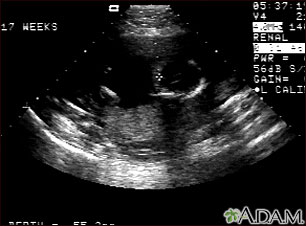

A pregnancy ultrasound is an imaging test that uses sound waves to create a picture of how a baby is developing in the womb (uterus). It is also used to check the female pelvic organs during pregnancy.

- These waves bounce off the body structures, including the developing baby, to create a picture on the ultrasound machine.

A pregnancy ultrasound may be done during the first 12 weeks of pregnancy to:

- Confirm a normal pregnancy

- Determine the baby's age

- Look for problems, such as ectopic pregnancies or the chances for a miscarriage

- Determine the baby's heart rate

- Look for multiple pregnancies (such as twins and triplets)

- Identify problems of the placenta, uterus, cervix, and ovaries

- Look for findings that might indicate an increased risk for Down syndrome

The developing baby, placenta, amniotic fluid, and surrounding structures appear normal for the gestational age.